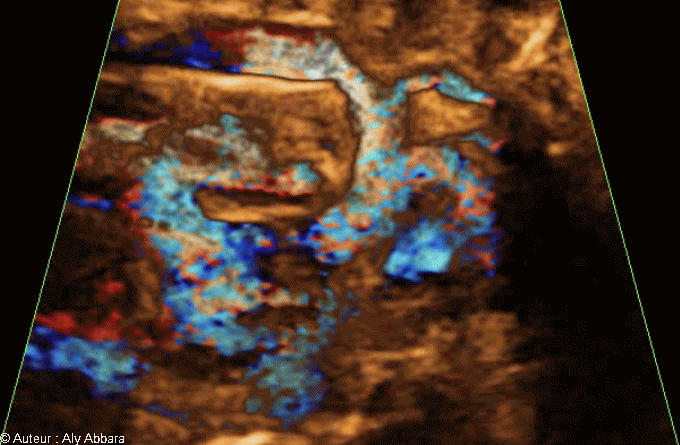

Images échographiques montrant l'aorte de son départ du ventricule gauche jusqu’à sa portion descendante en passant par sa crosse.

On observe sur cette image animée que la crosse aortique ne donne que deux branches au lieu des trois branches habituelles.

La poursuite du trajet de ces deux branches permet de conclure que :

* La première branche correspond, comme c'est l'habitude dans le cas normal, au tronc artériel brachio-céphalique qui se divise rapidement en artère subclavière droite et artère carotide commune droite.

* La deuxième branche, correspond également, comme c'est l'habitude dans le cas normal, à l'artère carotide commune gauche.

* La branche manquante (non repérable échographiquement dans ce cas là) correspond à l'artère subclavière gauche.

Pour mémoire : la crosse de l'aorte, au niveau de son bord supérieur, donne trois branches : le tronc brachio-céphalique, l'artère carotide commune gauche et l'artère subclavière gauche).

Il s'agit d'une fœtus de 34 SA souffrant d'une occlusion intestinale avec la présence, dans la fosse iliaque droite, d'un magma d'anses grêles hyperdenses, agglutinées et obstruées. On note également la présence d'une agénésie du rein droit.